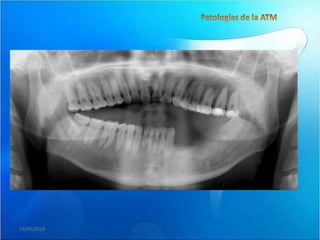

• En la vista

panorámica

de la

articulación

con radiologia

convencional

se observan

imágenes

radiopacas en

la articulación

del lado

izquierdo

(flecha)

• En las secciones sagitales observese la

disminución del espacio articular, el

aplanamiento y esclerosis de las superficies

articulares a predominio del lado izquierdo y

la disminución del recorrido condilar(vista

sagital a boca abierta).